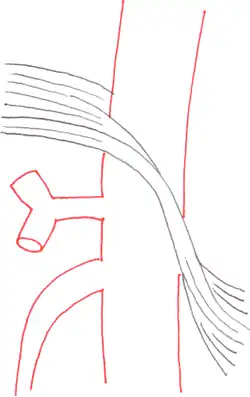

Das Ligamentum arcuatum medianum entspringt an der Basis des Zwerchfelles, dort wo der rechte und linke Zwerchfellschenkel (Crus dextrum et sinistrum) etwa in Höhe des 12. Brustwirbels zusammenkommen. Dieser Gewebebogen bildet die Vorderseite des Hiatus aorticus, durch den die Aorta mit dem Plexus aorticus abdominalis und der Ductus thoracicus ziehen.[2] Normalerweise sitzt das Ligamentum oberhalb des Abgangs des Truncus coeliacus, bei etwa 25 % der Menschen kreuzt das Ligament jedoch auf Höhe des Abgangs und engt dadurch die Arterie und benachbarte Strukturen, wie das Ganglion coeliacum ein. Bei einigen ist die Einengung so stark, dass die Krankheitssymptome entstehen.[1][3]

Die Befunde einer kurzstreckigen Einengung des Truncus coeliacus an seinem Abgang mit nachfolgender Erweiterung (poststenotische Dilatation), einer Einkerbung im oberen Aspekt des Truncus und eines hakenförmigen Verlaufes des Truncus unterstützen die Diagnose eines Truncus-coeliacus-Kompressionssyndroms.[1] Diese Bildkriterien sind in Exspiration betont und finden sich zum Teil sogar bei asymptomatischen Patienten, die nicht an dem Syndrom leiden.[1]

Auch müssen andere mögliche Differenzialdiagnosen bei einer abgangsnahen Einengung mit poststenotischer Dilatation, wie zum Beispiel arteriosklerotische Veränderungen, berücksichtigt werden.[1] Hier kann der hakenförmige Verlauf des Truncus coeliacus für die Unterscheidung hilfreich sein, wenn auch dieses Kriterium ebenfalls nicht pathognomonisch für das Truncus-coeliacus-Kompressionssyndrom ist. Die Häufigkeit für diese Anatomie bei normalen asymptomatischen Personen wird mit 10 bis 24 % angegeben.[1]